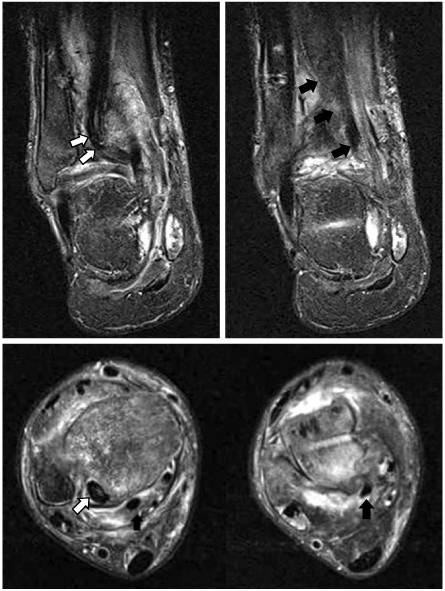

Fig. 5

Ankle MRI shows incarceration of posterior tibial tendon into the fibular groove of distal tibia (white arrows) and displaced flexor hallucis longus tendon (black arrows).

Fig. 5 Ankle MRI shows incarceration of posterior tibial tendon into the fibular groove of distal tibia (white arrows) and displaced flexor hallucis longus tendon (black arrows).